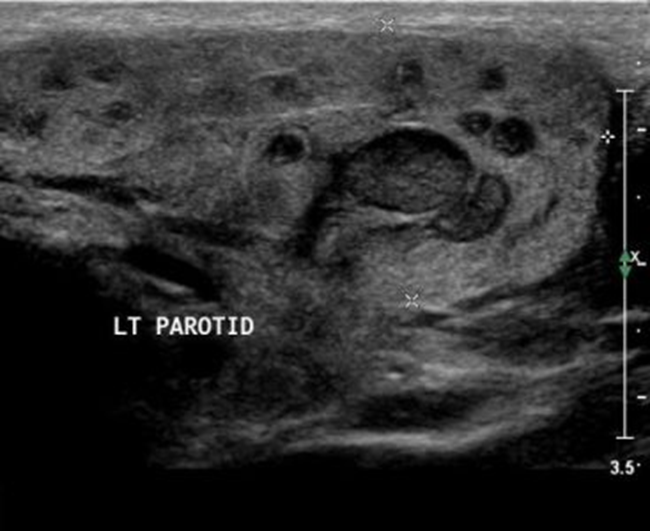

Эхографические признаки:

·        Увеличение размера пораженной железы

·        Понижение эхогенности (диффузно или части железы)

·        Снижение четкости контуров железы, дифференцировки анатомических образований.

Ультразвуковая картина при локальном снижении эхогенности (особенно в глубоких отделах околоушной железы) может напоминать злокачественное образование, однако при сопоставлении ультразвуковых данных с клиническими проявлениями и динамическом наблюдении за пациентом с интервалом в 3-4 недели, диагностические сомнения сводятся к нулю.